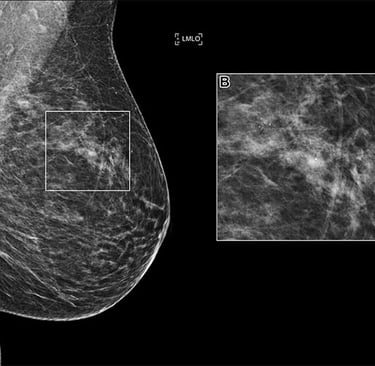

RSNA AI Challenge Models Can Independently Interpret Mammograms

Los algoritmos presentados para el Desafío de IA organizado por RSNA han demostrado un excelente desempeño para detectar cánceres de mama en imágenes de mamografía, aumentando la sensibilidad de detección y manteniendo bajas tasas de recuperación, según un estudio publicado en Radiology.